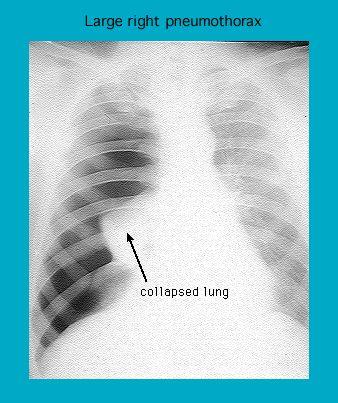

Radiographie montrant un pneumothorax droit